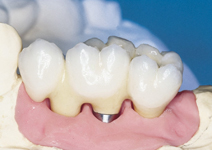

Náhrada jednoho zubu pomocí implantátu je možná také v postranním úseku chrupu. Při ztrátě většího počtu zubů ve frontálním nebo postranním úseku může být mezer uzavřena větším počtem jednotlivých implantátů.

Při ošetření pomocí jednotlivých implantátů zůstávají sousední zuby neporušené – intaktní. Při klasickém ošetření pomocí můstků musejí být tyto zuby obroušeny!